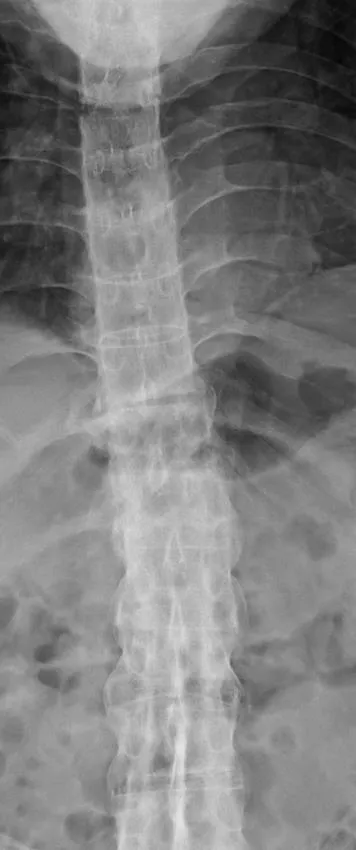

Age: 72 years | Gender: Male |

Clinical problem: Back pain following a fall | |

Images in exam case: Plain radiograph (4), CT (2) | |

FINDINGS

- 1. X-ray thoracolumbar spine:

- a. Marginal syndesmophytes

- b. Ossification of the interspinous ligament – ‘dagger’ sign

- c. Ossification of the anterior longitudinal ligament

- d. Fusion of both sacroiliac joints

- e. Fracture through mid-thoracic intervertebral disc with retrolisthesis of superior vertebra.

DIAGNOSIS

- 1. Ankylosing spondylitis, acute fracture through D5/6 extending through the posterior elements. This is an unstable fracture as all three vertebral columns are disrupted.

Ankylosing spondylitis is a regular feature of the FRCR 2B examination, either as a written case or in the viva. The scenarios involved could be bilateral symmetrical sacroiliac joint erosion, sclerosis or fusion, erosion of the anterosuperior corner of the vertebra on lateral radiograph (Romanus sign), sclerosis of the anterosuperior corner and periostitis of the waist giving rise to vertebral ‘squaring’, syndesmophyte formation leading to ‘bamboo spine’, intervertebral disc calcification, ossification of the anterior longitudinal, posterior longitudinal, interspinous and supraspinous ligaments, kyphosis and facet joint fusion. Other skeletal features include erosions of the symphysis pubis and ischial tuberosities, asymmetrical erosive oligoarthritis, atlanto-axial dislocation and osteoporosis. In a traumatic setting, the fracture line may run through the intervertebral disc space right through into the posterior elements, and may be missed if one is not vigilant. Clinically occult fractures can also occur, leading to mobile non-union (pseudoarthrosis) – the so-called Anderson lesion.